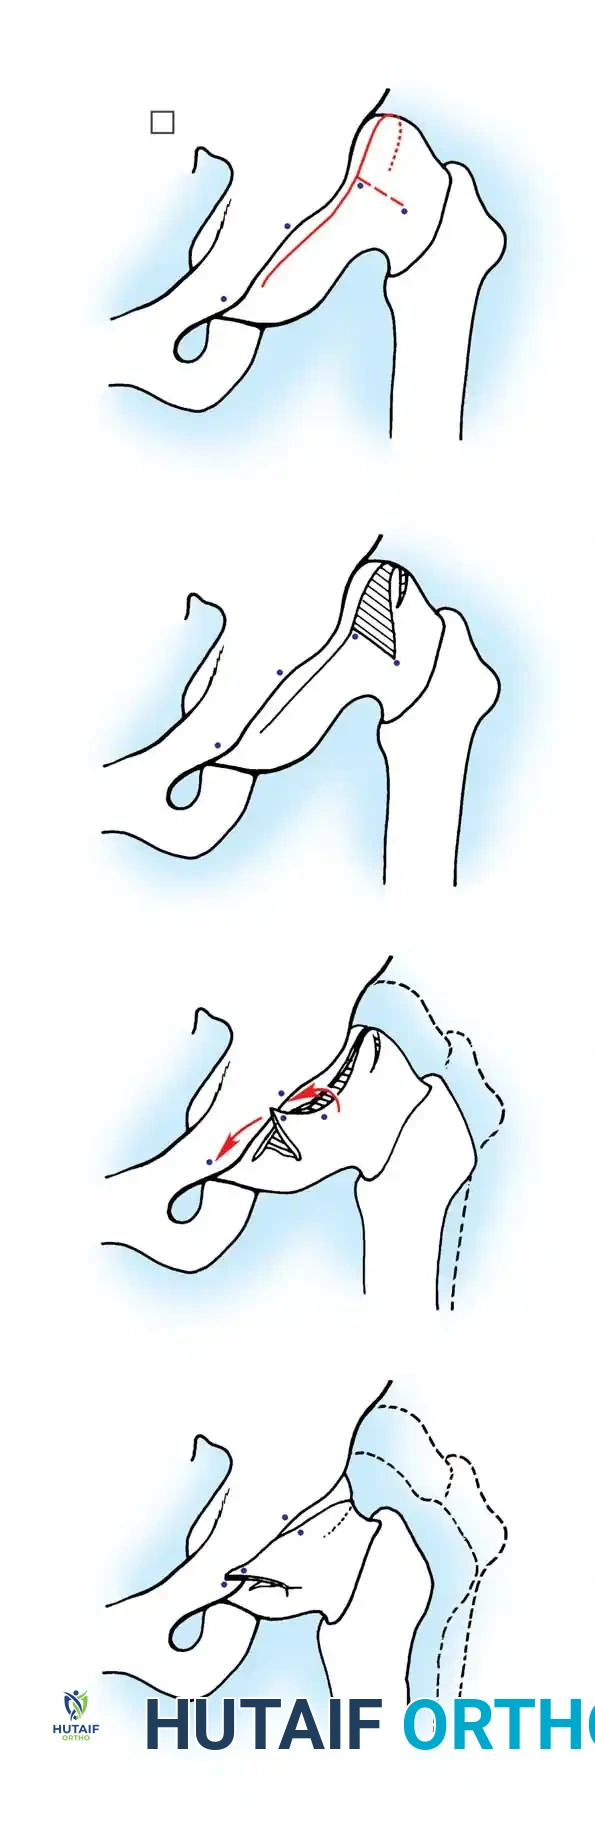

- Salter Innominate Osteotomy:

- Indications: Children aged 18 months to 6 years with a congruous joint but anterolateral acetabular deficiency.

- Biomechanics: A complete transverse cut is made through the ilium just above the acetabulum to the sciatic notch. The entire acetabulum is rotated anteriorly and laterally, hinging on the pubic symphysis.

- Fixation: A triangular bone graft (harvested from the iliac crest) is placed in the osteotomy site, and the construct is stabilized with threaded Kirschner wires.

Diagrammatic representation of the Salter Innominate Osteotomy. Note the complete iliac cut and the placement of the triangular bone graft to redirect the acetabulum.

- Pemberton Pericapsular Osteotomy:

- Indications: Severe dysplasia with a capacious acetabulum.

- Biomechanics: An incomplete cut is made through the ilium, curving down to the triradiate cartilage, which acts as a hinge. This reshapes the acetabular roof, reducing its volume and improving anterolateral coverage.